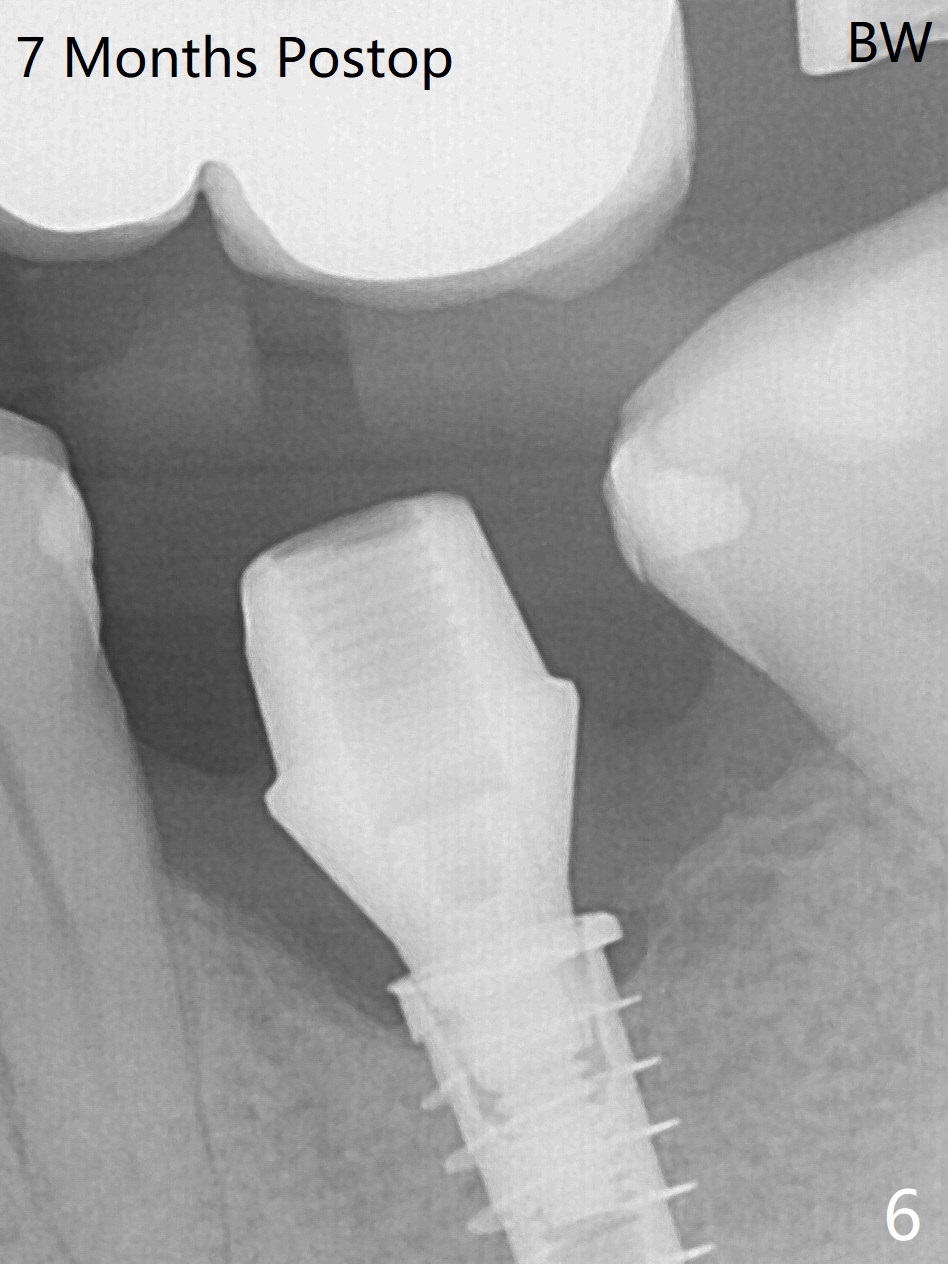

While the mesial ridge is relatively wide associated with residual root at #19 (Fig.1 <), the distal one is narrow (*). Osteotomy is initiated distal to the mesial socket (Fig.2,3 *). Due to the narrow ridge, a 4.5x11 mm implant is placed (Fig.4); before as well as after placement of a 6x4(3) mm abutment, the mesial socket (*) is filled with Vera graft and autogenous bone as well as collagen plug. Following suturing, periodontal dressing is applied to the wound. There is no apparent bone loss 7 months postop (Fig.5,6) or 14 months post cementation (Fig.7). In fact the abutment has been incompletely seated (Fig.5-8), which may be related to #13 failure. The ridge appears to be narrow for the 4.5 mm implant 1.5 years post cementation (Fig.9). When a lady looks skinny with sign of the narrow ridge, choose an implant as narrow as possible.